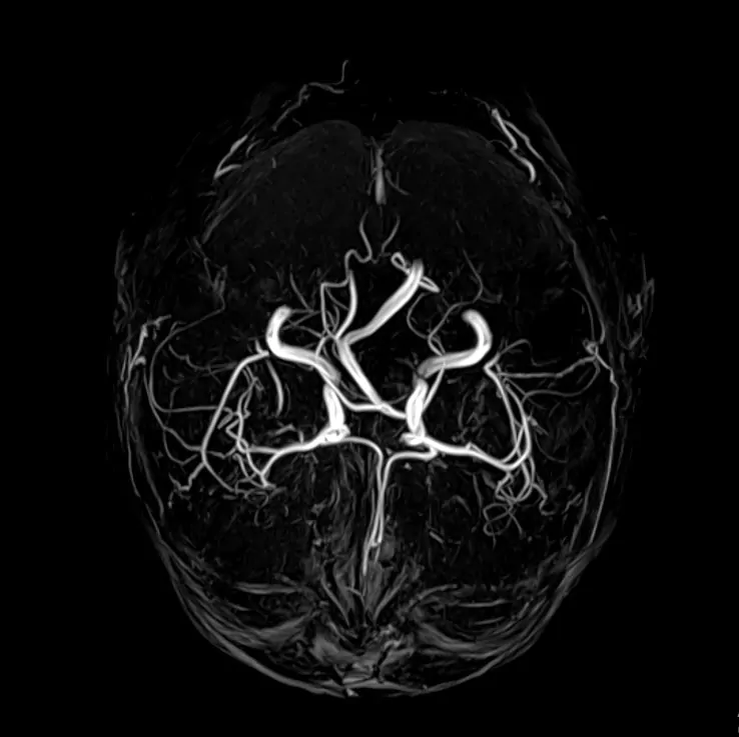

МРТ сосудов, в отличие от КТ, является наиболее безопасным исследованием и не сопровождается лучевой нагрузкой, и зачастую нет необходимости вводить контрастные вещества для повышения визуализации. В этой связи, МР-ангиографию можно делать пациентам с сопутствующими патологиями, беременным и детям необходимое количество раз. Также, немало важной особенностью МРТ является возможность оценки не только самих сосудов, но и их взаимодействия с тканями головного мозга. Стоит отметить, для МРТ характерна определенная область исследования и время, затрачиваемое на исследование, составляет 10-15 минут.

МРТ головы